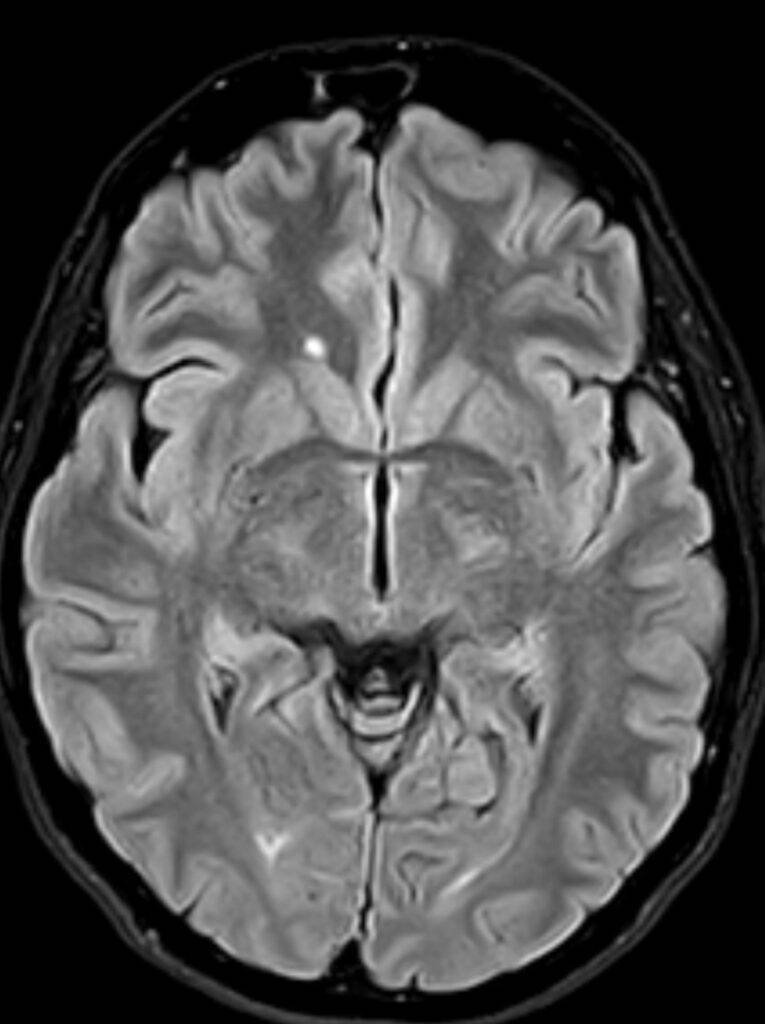

- Schlaganfälle und Blutungen: Auf den MRT-Bildern vom Kopf sind frische Schlaganfälle, Hirnblutungen und andere vaskuläre Probleme im Gehirn zu erkennen.

- Entzündungen und Infektionen: Entzündliche Zustände im Gehirn, wie Enzephalitis oder Abszesse, können durch die MRT Kopf Untersuchung identifiziert werden.

- Degenerative Erkrankungen: Die Kopf MRT kann bei der Diagnose degenerativer Erkrankungen wie Alzheimer oder Multipler Sklerose (Link) helfen, indem sie Veränderungen im Gehirngewebe zeigt.